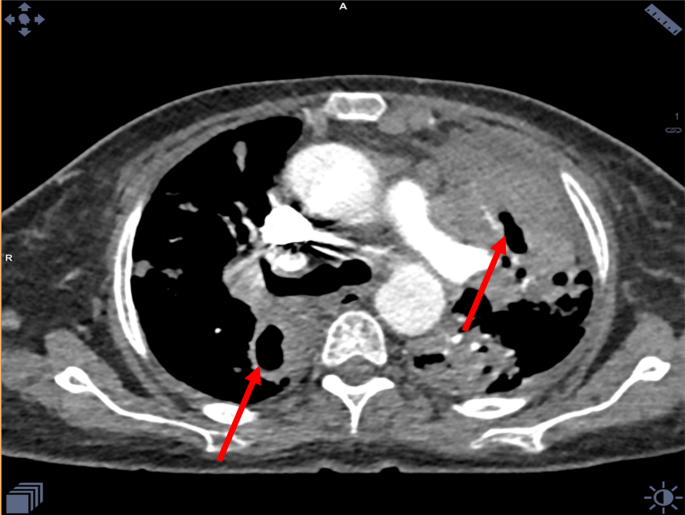

A 58-year-old female patient, with 20 pack-year smoking history, and type 2 Diabetes mellitus for 2 years. She presented in 2015, with an incidental right apical lung mass suggestive of Pancoast tumor as demonstrated on her chest CT (Fig. 1a, b) following abnormal chest X-ray. The patient refused further investigations at the time. 3 years later, she was admitted to with sepsis secondary to acute cholecystitis.

a, b Chest CT showing a well-defined right apical mass lesion with pleural invasion and possible mediastinal extension, suggestive of Pancoast tumor (red arrow)